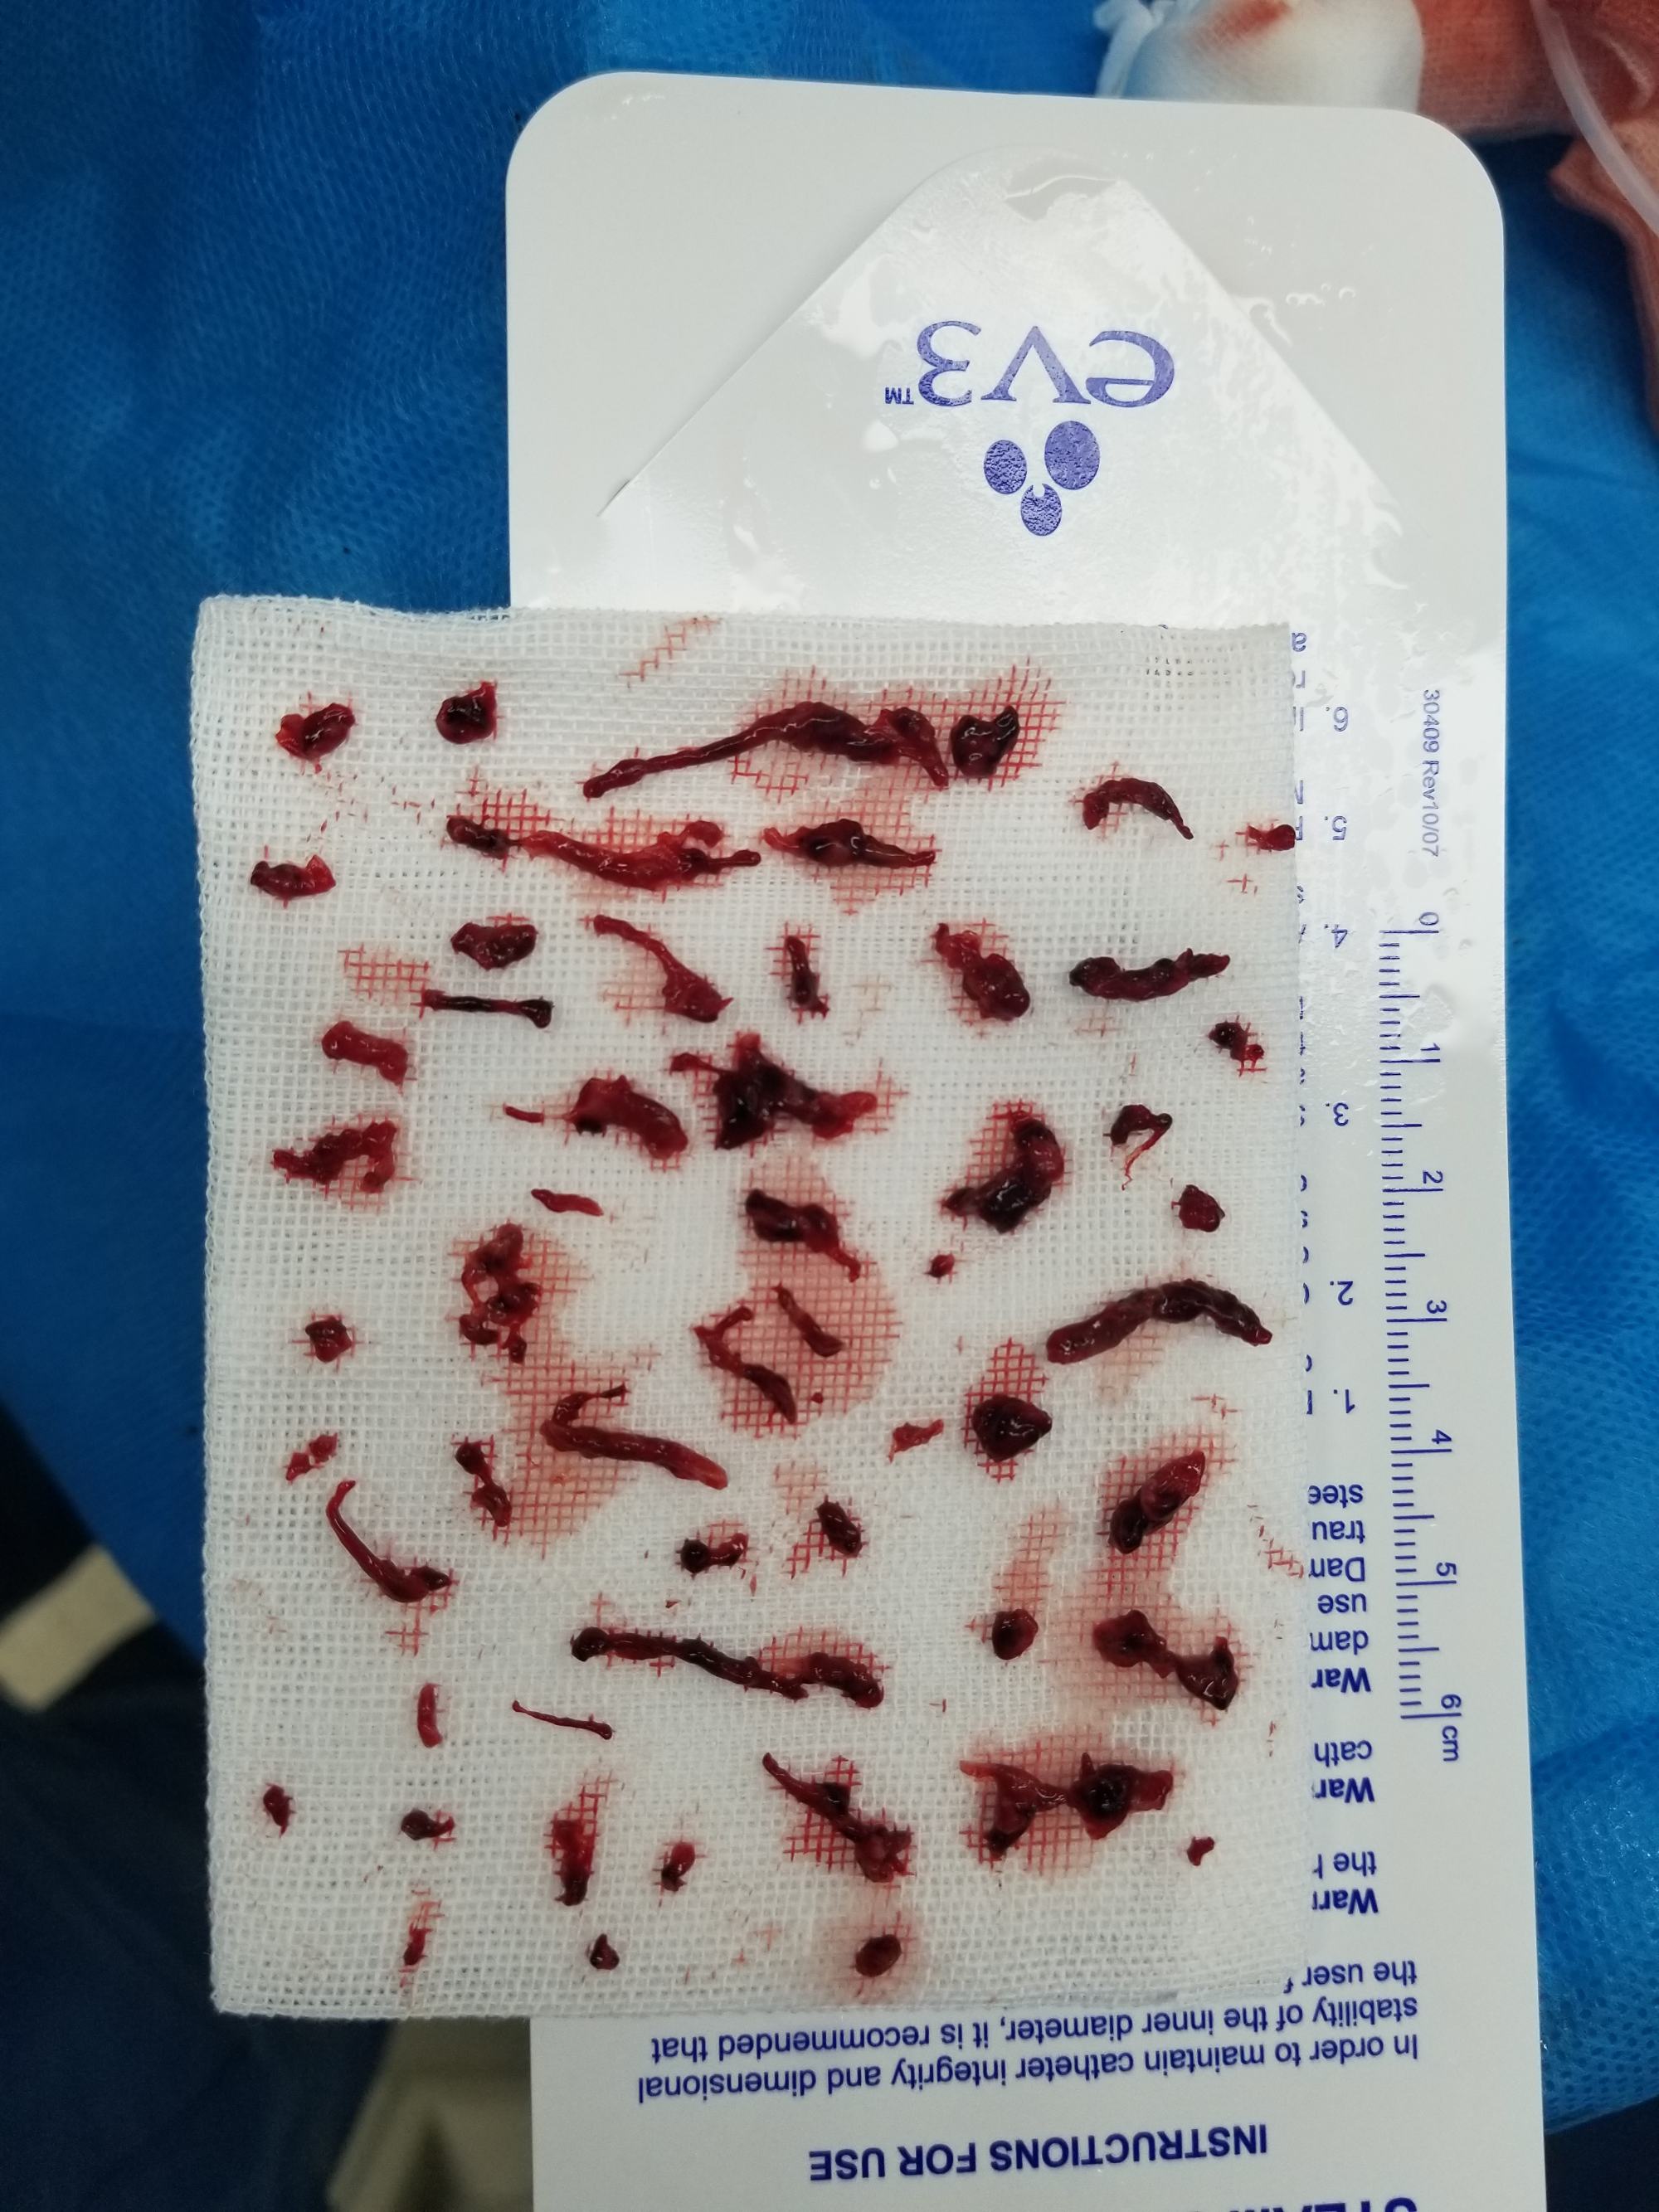

支架取出部分血栓,抽吸导管抽出大量血栓

抽吸出的血栓